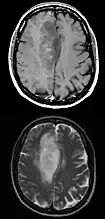

| Coronal MRI with contrast of a glioblastoma in a 15-year-old male | |

Axial post-contrast T1 (top) and T2 (bottom) weighted MRI showing an IDH1 mutant frontal lobe glioblastoma with sparse enhancement despite large size. -